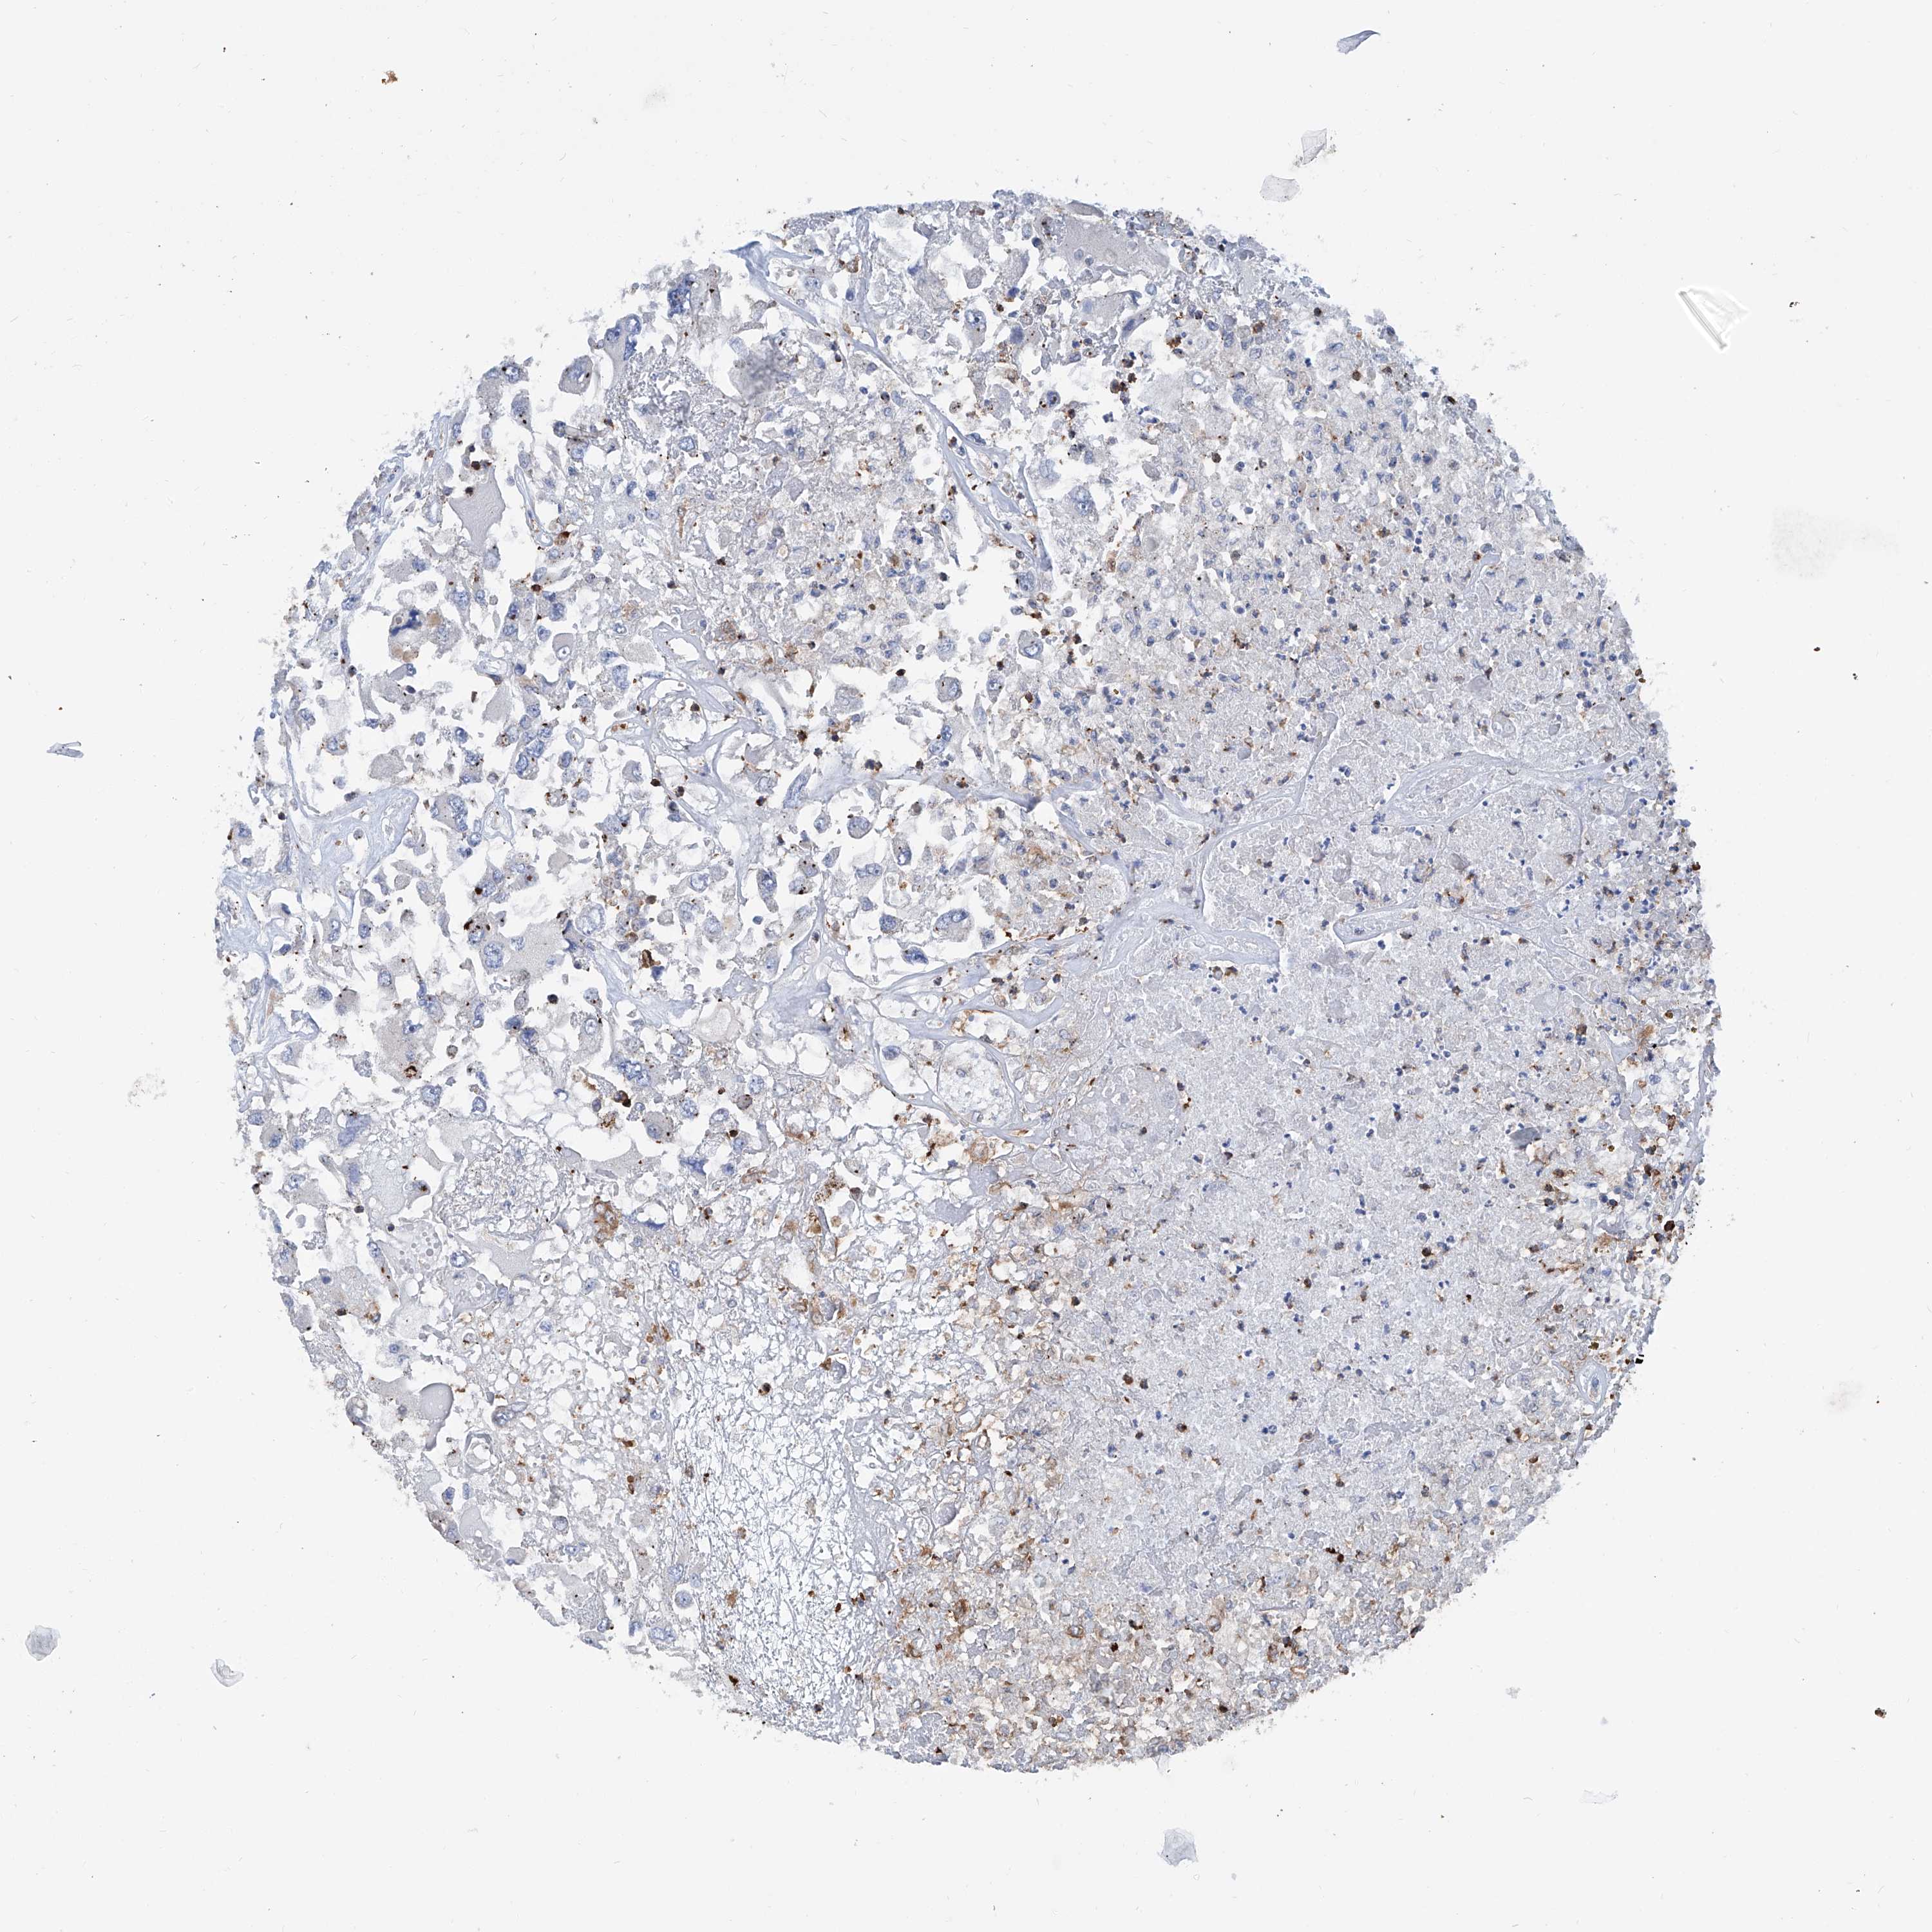

KIDNEY RENAL CLEAR CELL CARCINOMA (VALIDATION) - Interactive survival scatter ploti

The Survival Scatter plot shows the clinical status (i.e. dead or alive) for all individuals in the patient cohort, based on the same data that underlies the corresponding Kaplan-Meier plots. Patients that are alive at last time for follow-up are shown in blue and patients who have died during the study are shown in red.

The x-axis shows the expression levels (FPKM) of the investigated gene in the tumor tissue at the time of diagnosis. The y-axis shows the follow-up time after diagnosis (years). Both axes are complimented with kernel density curves demonstrating the data density over the axes. The top density plot shows the expression levels (FPKM) distribution among dead (red) and alive patients (blue). The right density plot shows the data density of the survived years of dead patients with high and low expression levels respectively, stratified using the cutoff indicated by the vertical dashed line through the Survival Scatter plot. This cutoff is automatically defined based on the FPKM cutoff that minimizes the p-score. The cutoff can be changed by dragging the vertical line or by entering a cutoff value in the square labeled "Current cut-off".

Under the Survival Scatter plot the p-score landscape (black curve; left axis) is shown together with dead median separation (red curve; right axis). Dead median separation is the difference in median mRNA expression between patients who have died with high and low expression, respectively. It is calculated as follows: median FPKM expression of dead patients with high expression - median FPKM expression of dead patients with low expression. This is intended to aid the user in visually exploring custom cutoffs and the associated p-scores and dead median separation.

Individual patient data is displayed and can be filtered by clicking on one or more of the category buttons on the top of the page. Categories describing expression level and patient information include: high, low, alive, dead, female, male and tumor stages. The scale of the x-axis can be toggled between linear and log-scale by clicking on the "x log" button. Mouse-over function shows TCGA ID, patient information and mRNA expression (FPKM) for each patient.

& Survival analysisi

Kaplan-Meier plots summarize results from analysis of correlation between mRNA expression level and patient survival. Patients were divided based on level of expression into one of the two groups "low" (under cut off) or "high" (over cut off). X-axis shows time for survival (years) and y-axis shows the probability of survival, where 1.0 corresponds to 100 percent.

ZNF484 is validated prognostic, high expression is favorable in Kidney Renal Clear Cell Carcinoma (validation)

Best expression cut offi

Based on the FPKM value of each gene, patients were classified into two groups and association between prognosis (survival) and gene expression (FPKM) was examined. The best expression cut-off refers the FPKM value that yields maximal difference with regard to survival between the two groups at the lowest log-rank P-value. Best expression cut-off was selected based on survival analysis .

When clicking on this number, the vertical dashed line indicating cut-off, the interactive survival plot, and the Kaplan-Meier curve will be adjusted to show results based on the best expression cut-off.

: 3.72

TCGA RNA samplesi

RNA-seq data is reported as average FPKM (number Fragments Per Kilobase of exon per Million reads), generated by the The Cancer Genome Atlas (TCGA) .

Normal distribution across the dataset is visualized with box plots, shown as median and 25th and 75th percentiles. Points are displayed as outliers if they are above or below 1.5 times the interquartile range. FPKM values of the individual samples are presented next to the box plot.

Average pTPM 3.5

Number of samples 100